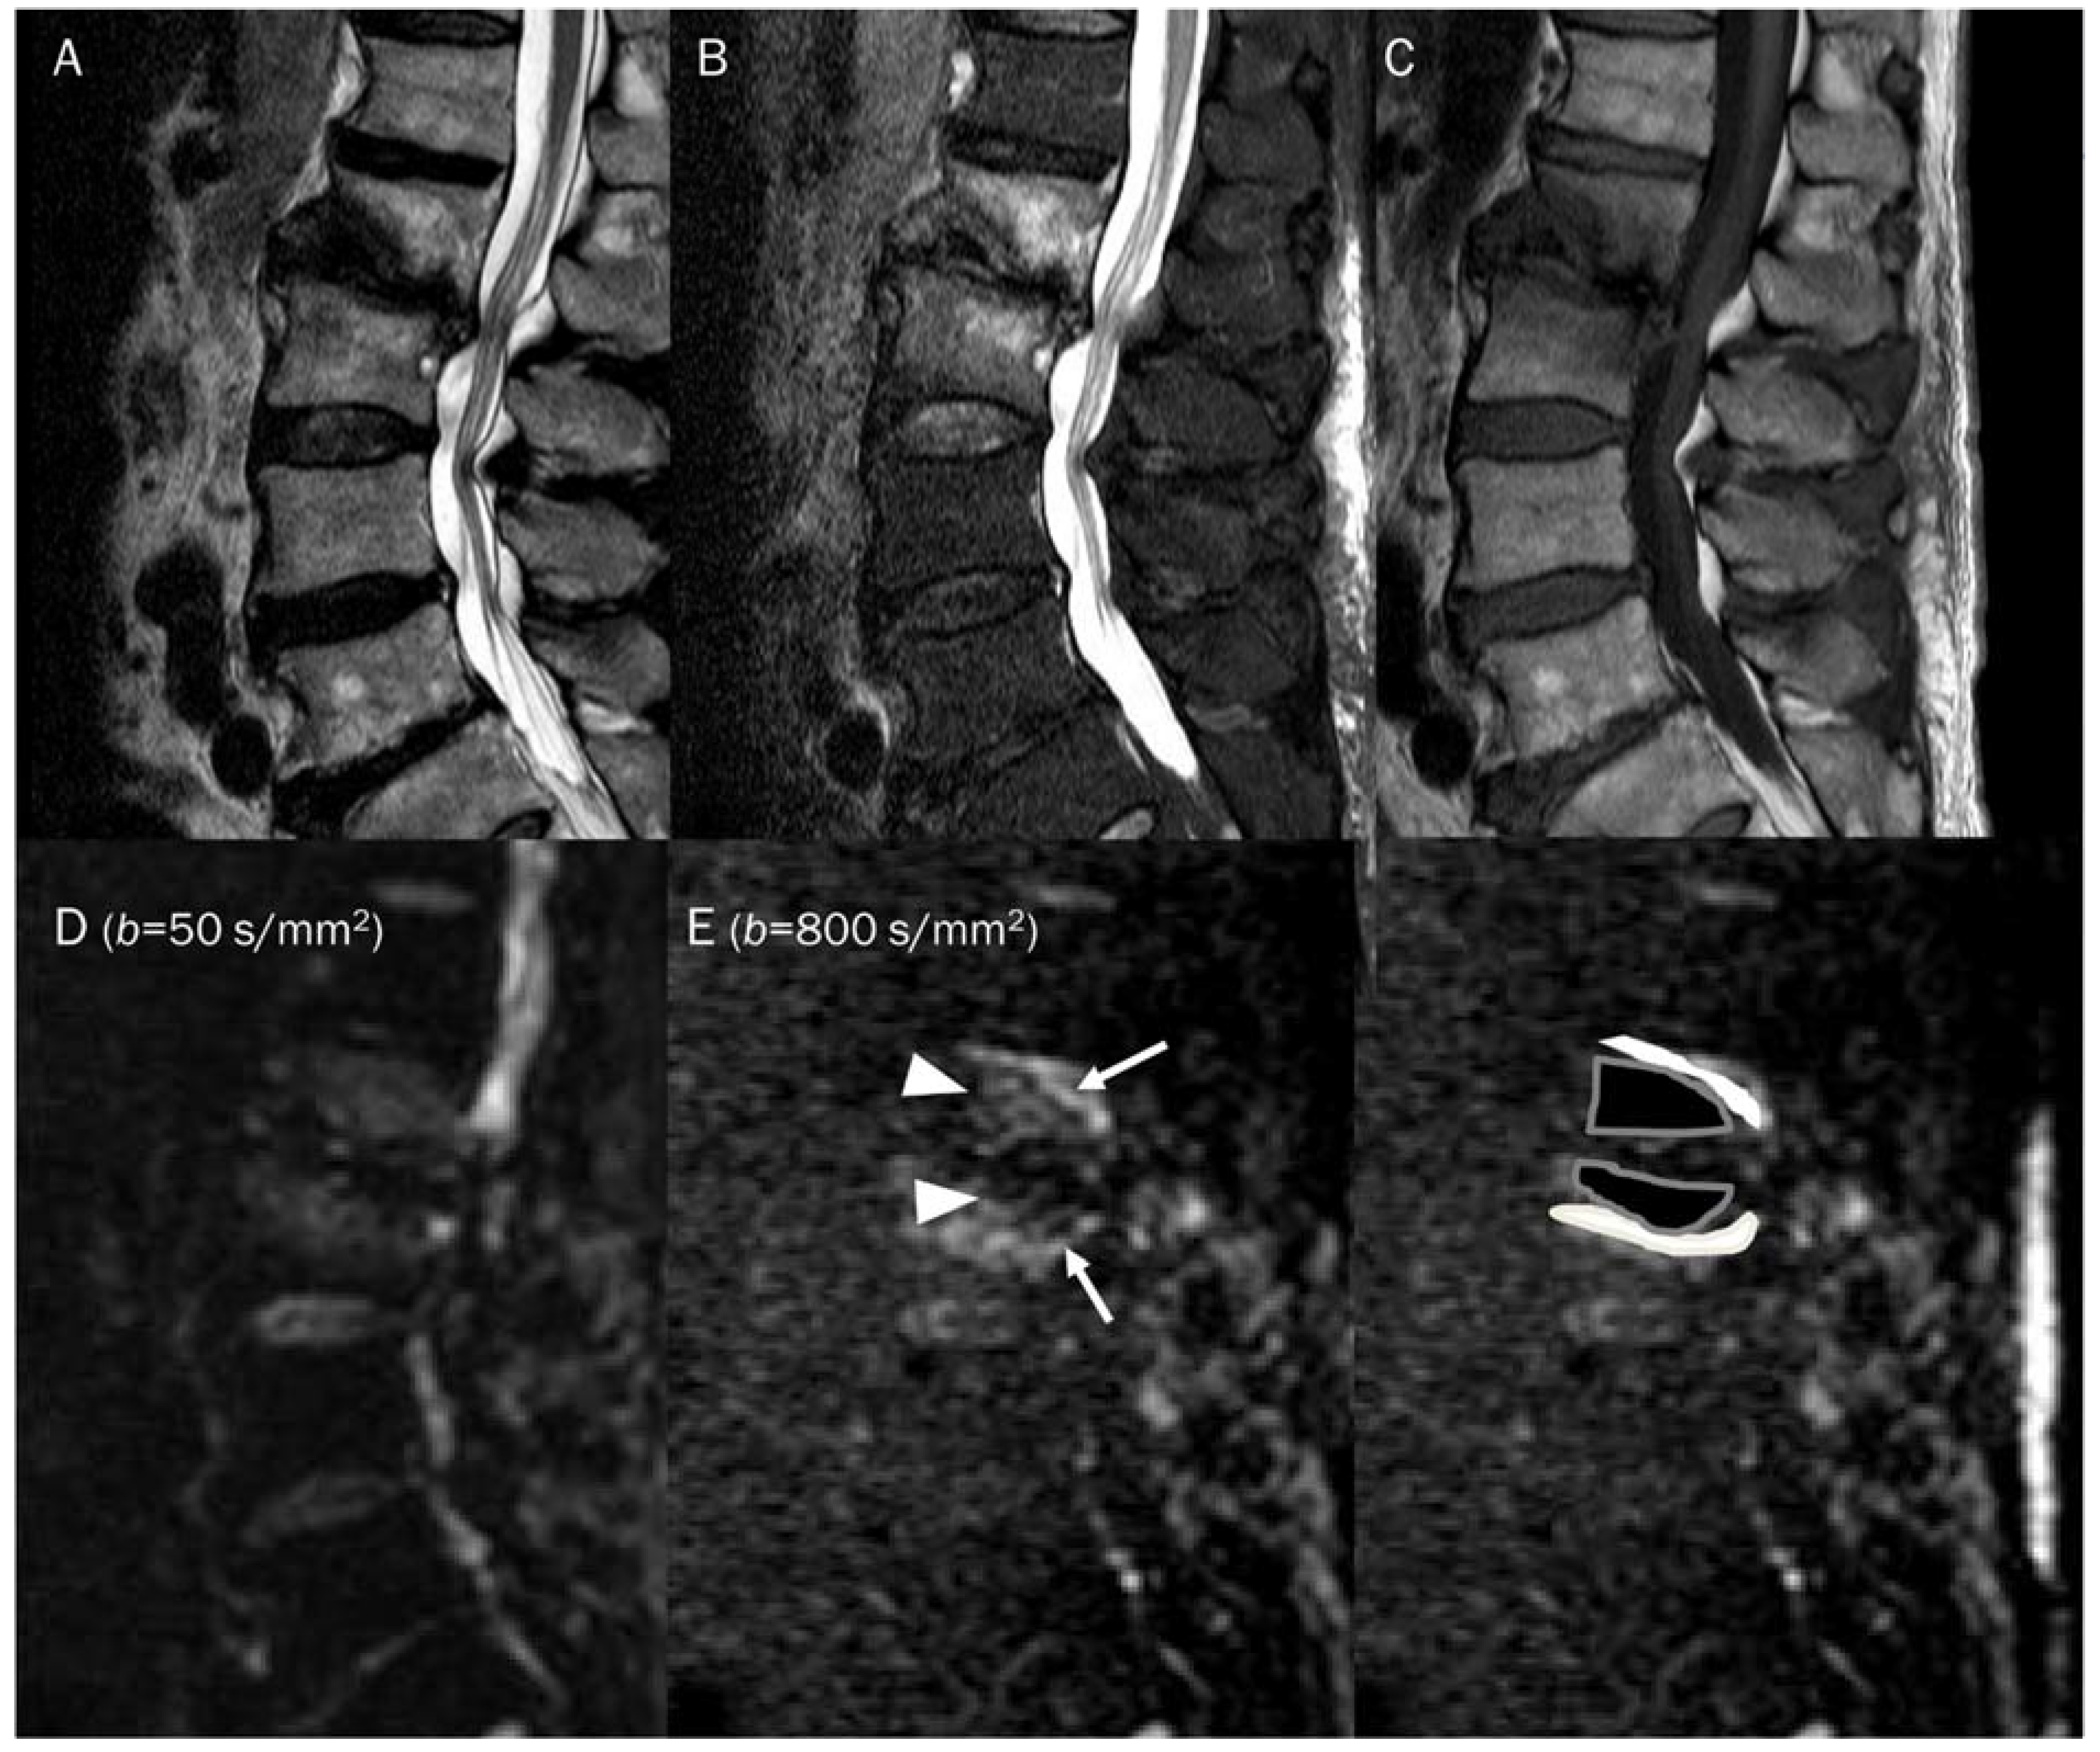

7.4. Vertebral Endplate Changes

- Oztekin, O.; Calli, C.; Kitis, O.; Adibelli, Z.H.; Eren, C.S.; Apaydin, M.; Zileli, M.; Yurtseven, T. Reliability of diffusion weighted MR imaging in differentiating degenerative and infectious end plate changes. Radiol. Oncol. 2010, 44, 97–102. [Google Scholar] [CrossRef]

- Patel, K.B.; Poplawski, M.M.; Pawha, P.S.; Naidich, T.P.; Tanenbaum, L.N. Diffusion-weighted MRI “claw sign” improves differentiation of infectious from degenerative modic type 1 signal changes of the spine. AJNR Am. J. Neuroradiol. 2014, 35, 1647–1652. [Google Scholar] [CrossRef]